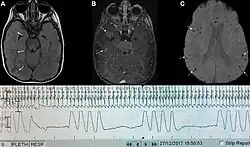

| Graph showing ataxic respirations and other pathological breathing patterns. | |

Ataxic respirations, also known as Biot's respirations or Biot's breathing, is an abnormal pattern of breathing characterized by variable tidal volume, random apneas, and no regularity.[1] It is named for Camille Biot, who characterized it in 1876.[2][3] Biot's respiration is caused by damage to the medulla oblongata and pons due to trauma, stroke, opioid use, and increased intracranial pressure due to uncal or tentorial herniation.[1][4] Often this condition is also associated with meningitis.[2] In common medical practice, Biot's respiration is often mistaken for Cheyne–Stokes respiration, part of which may have been caused by them both being described by the same person and subtle differences between the types of breathing.[1][3]

Ataxic respirations are caused by damage to the medulla oblongata (respiratory center of the brainstem) due to strokes or trauma. It generally indicates a poor prognosis and usually progresses to complete apnea.[7]